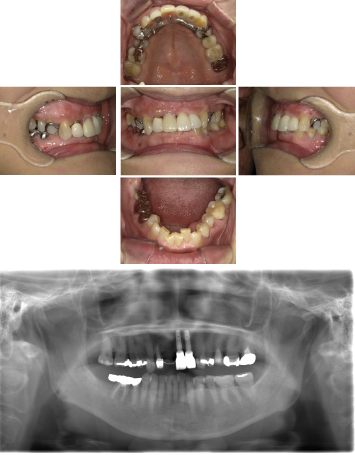

50代 インプラント治療(右上3左上3のみGBR)

| 年代・性別 | 50代・男性 |

| 主訴 | 入れ歯が合わず毎日ヨーグルトしか食べることができないので、しっかり咬めるインプラントにしたい。 |

| 部位 | 右下⑦⑥5④ 上顎③2①①2③ 左下67 |

| 治療期間 | 約9ヶ月 |

| 費用 | ¥4,273,500(税込) |

| 副作用・リスク |